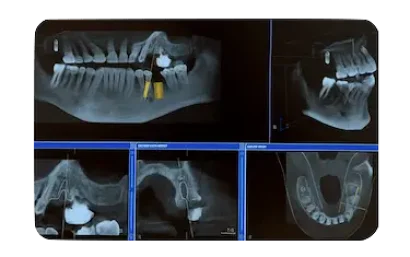

En primer lugar, te citamos en nuestra clínica para una valoración inicial sin coste.En esta visita realizamos una exploración oral completa y un estudio radiológico para determinar si eres candidato a un implante dental de carga inmediata y definir el plan más adecuado en tu caso. - Planificación personalizada del tratamiento.

Tras analizar los resultados del estudio, te explicamos de forma clara la propuesta de tratamiento, las distintas opciones disponibles y el presupuesto.Si aceptas el plan, programamos la intervención quirúrgica en función de tus necesidades clínicas. - Colocación del implante dental.